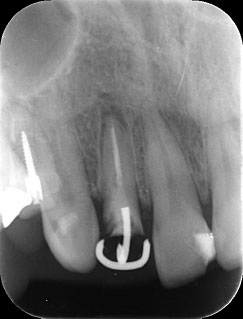

残存歯質はないが、歯根は長いことを確認。

MTM治療開始時と終了後。右の根尖の透過像が実際に歯が動いた部分。